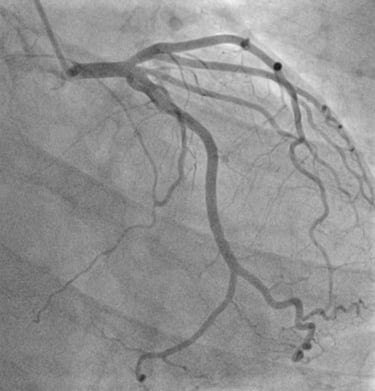

CORONAROGRAFIA

La Coronarografia è l’esame piu’ approfondito per valutare la presenza di restringimenti (“stenosi”) a carico delle arterie coronarie, ovvero delle arterie che nutrono il cuore. Viene effettuata tramite utilizzo di appositi cateteri che vengono inseriti attraverso l'arteria radiale o femorale. Per acquisire le immagini viene utilizzato un liquido chiamato “mezzo di contrasto” che opacizza il lume delle arterie mescolandosi al sangue. Le immagini vengono acquisite da un macchinario che emette una debole radiazione e registra le immagini.